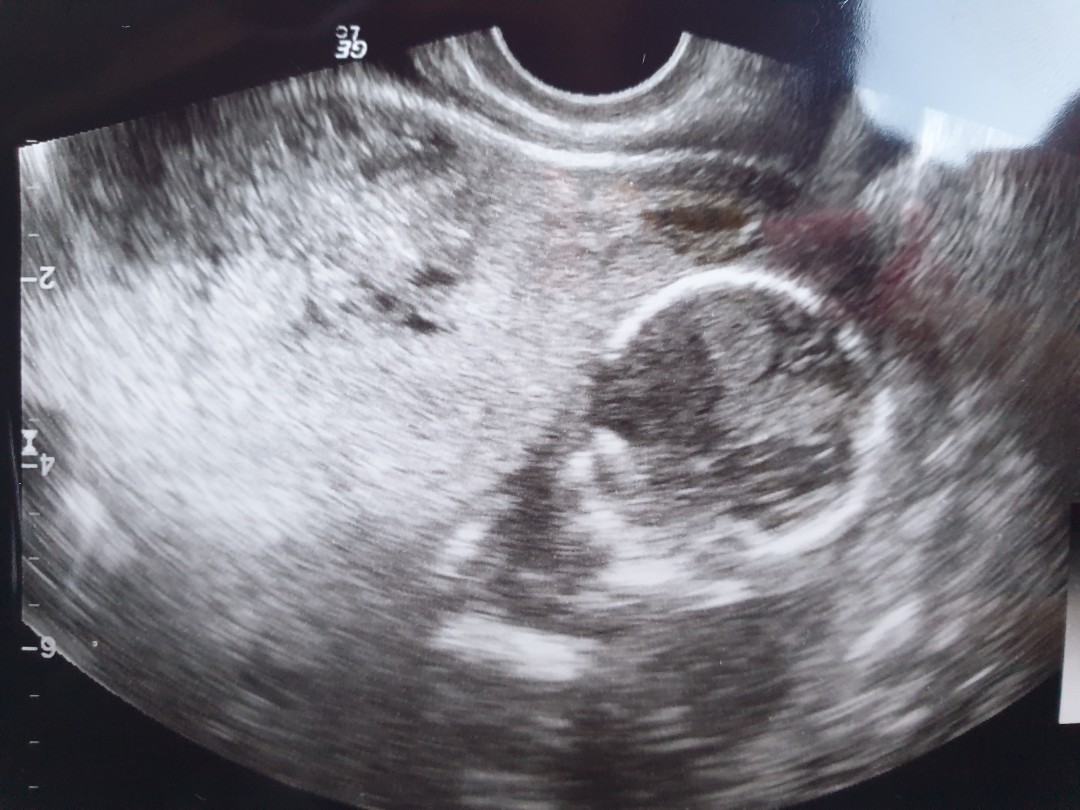

8วีค+5วันค่ะ